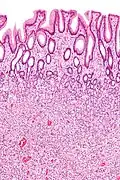

| Type de polype | Apparence histologique | Risque de malignité | Coupe histologique | Syndromes | |

|---|---|---|---|---|---|

| Hyperplasique | Cryptes dentées non-ramifiées | Non | ![]() |

Hyperplasique polypose syndrome | |

| Adénome tubulaire (villositaire, tubulovilleux) | Glandes tubulaires avec des noyaux allongés (au moins à faible teneur atypie) | Oui | ![]() |

||